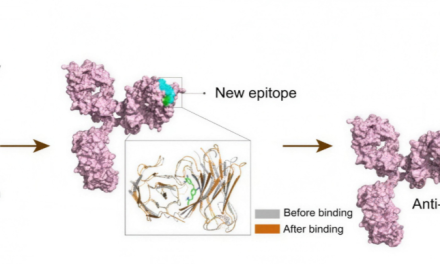

Ein internationales Forscherteam um Prof. David Baker hat mit Hilfe von Künstlicher Intelligenz...